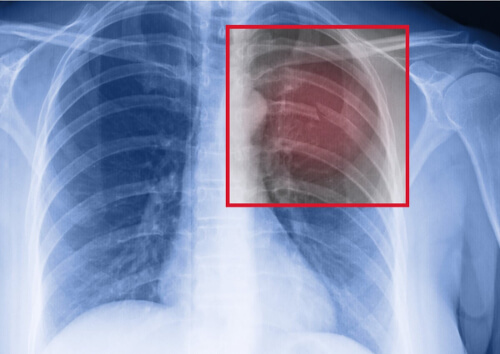

Jeśli jesteś sportowcem i doszło u Ciebie do naprężeniowego złamania żebra, pierwszą rzeczą jaką musisz zrobić, jest skonsultowanie się z lekarzem. Lekarz zleci prześwietlenie klatki piersiowej, aby potwierdzić uraz, i na jego podstawie oceni jego zakres.